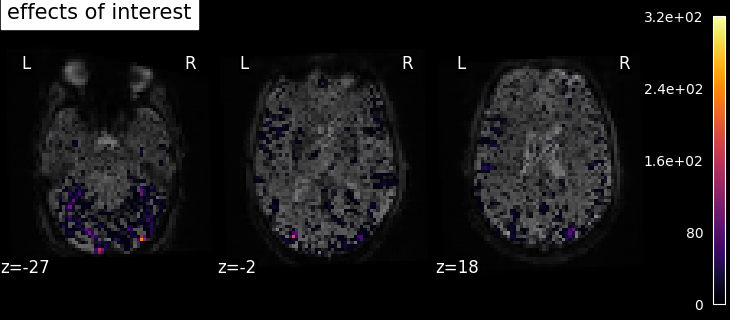

To get more interesting results out of the GLM model, contrasts can be computed between regressors of interest. The nilearn.glm.first_level.FirstLevelModel.compute_contrast function can be used for that. First, the contrasts of interest must be defined. In the spm_multimodal_fmri dataset referenced above, subjects are presented with ‘normal’ and ‘scrambled’ faces. The basic contrasts that can be constructed are the main effects of ‘normal faces’ and ‘scrambled faces’. Once the basic_contrasts have been set up, we can construct more interesting contrasts like ‘normal faces - scrambled faces’.

The activation maps from these 3 contrasts is presented below:

../_images/sphx_glr_plot_spm_multimodal_faces_002.png ../_images/sphx_glr_plot_spm_multimodal_faces_003.png ../_images/sphx_glr_plot_spm_multimodal_faces_004.png